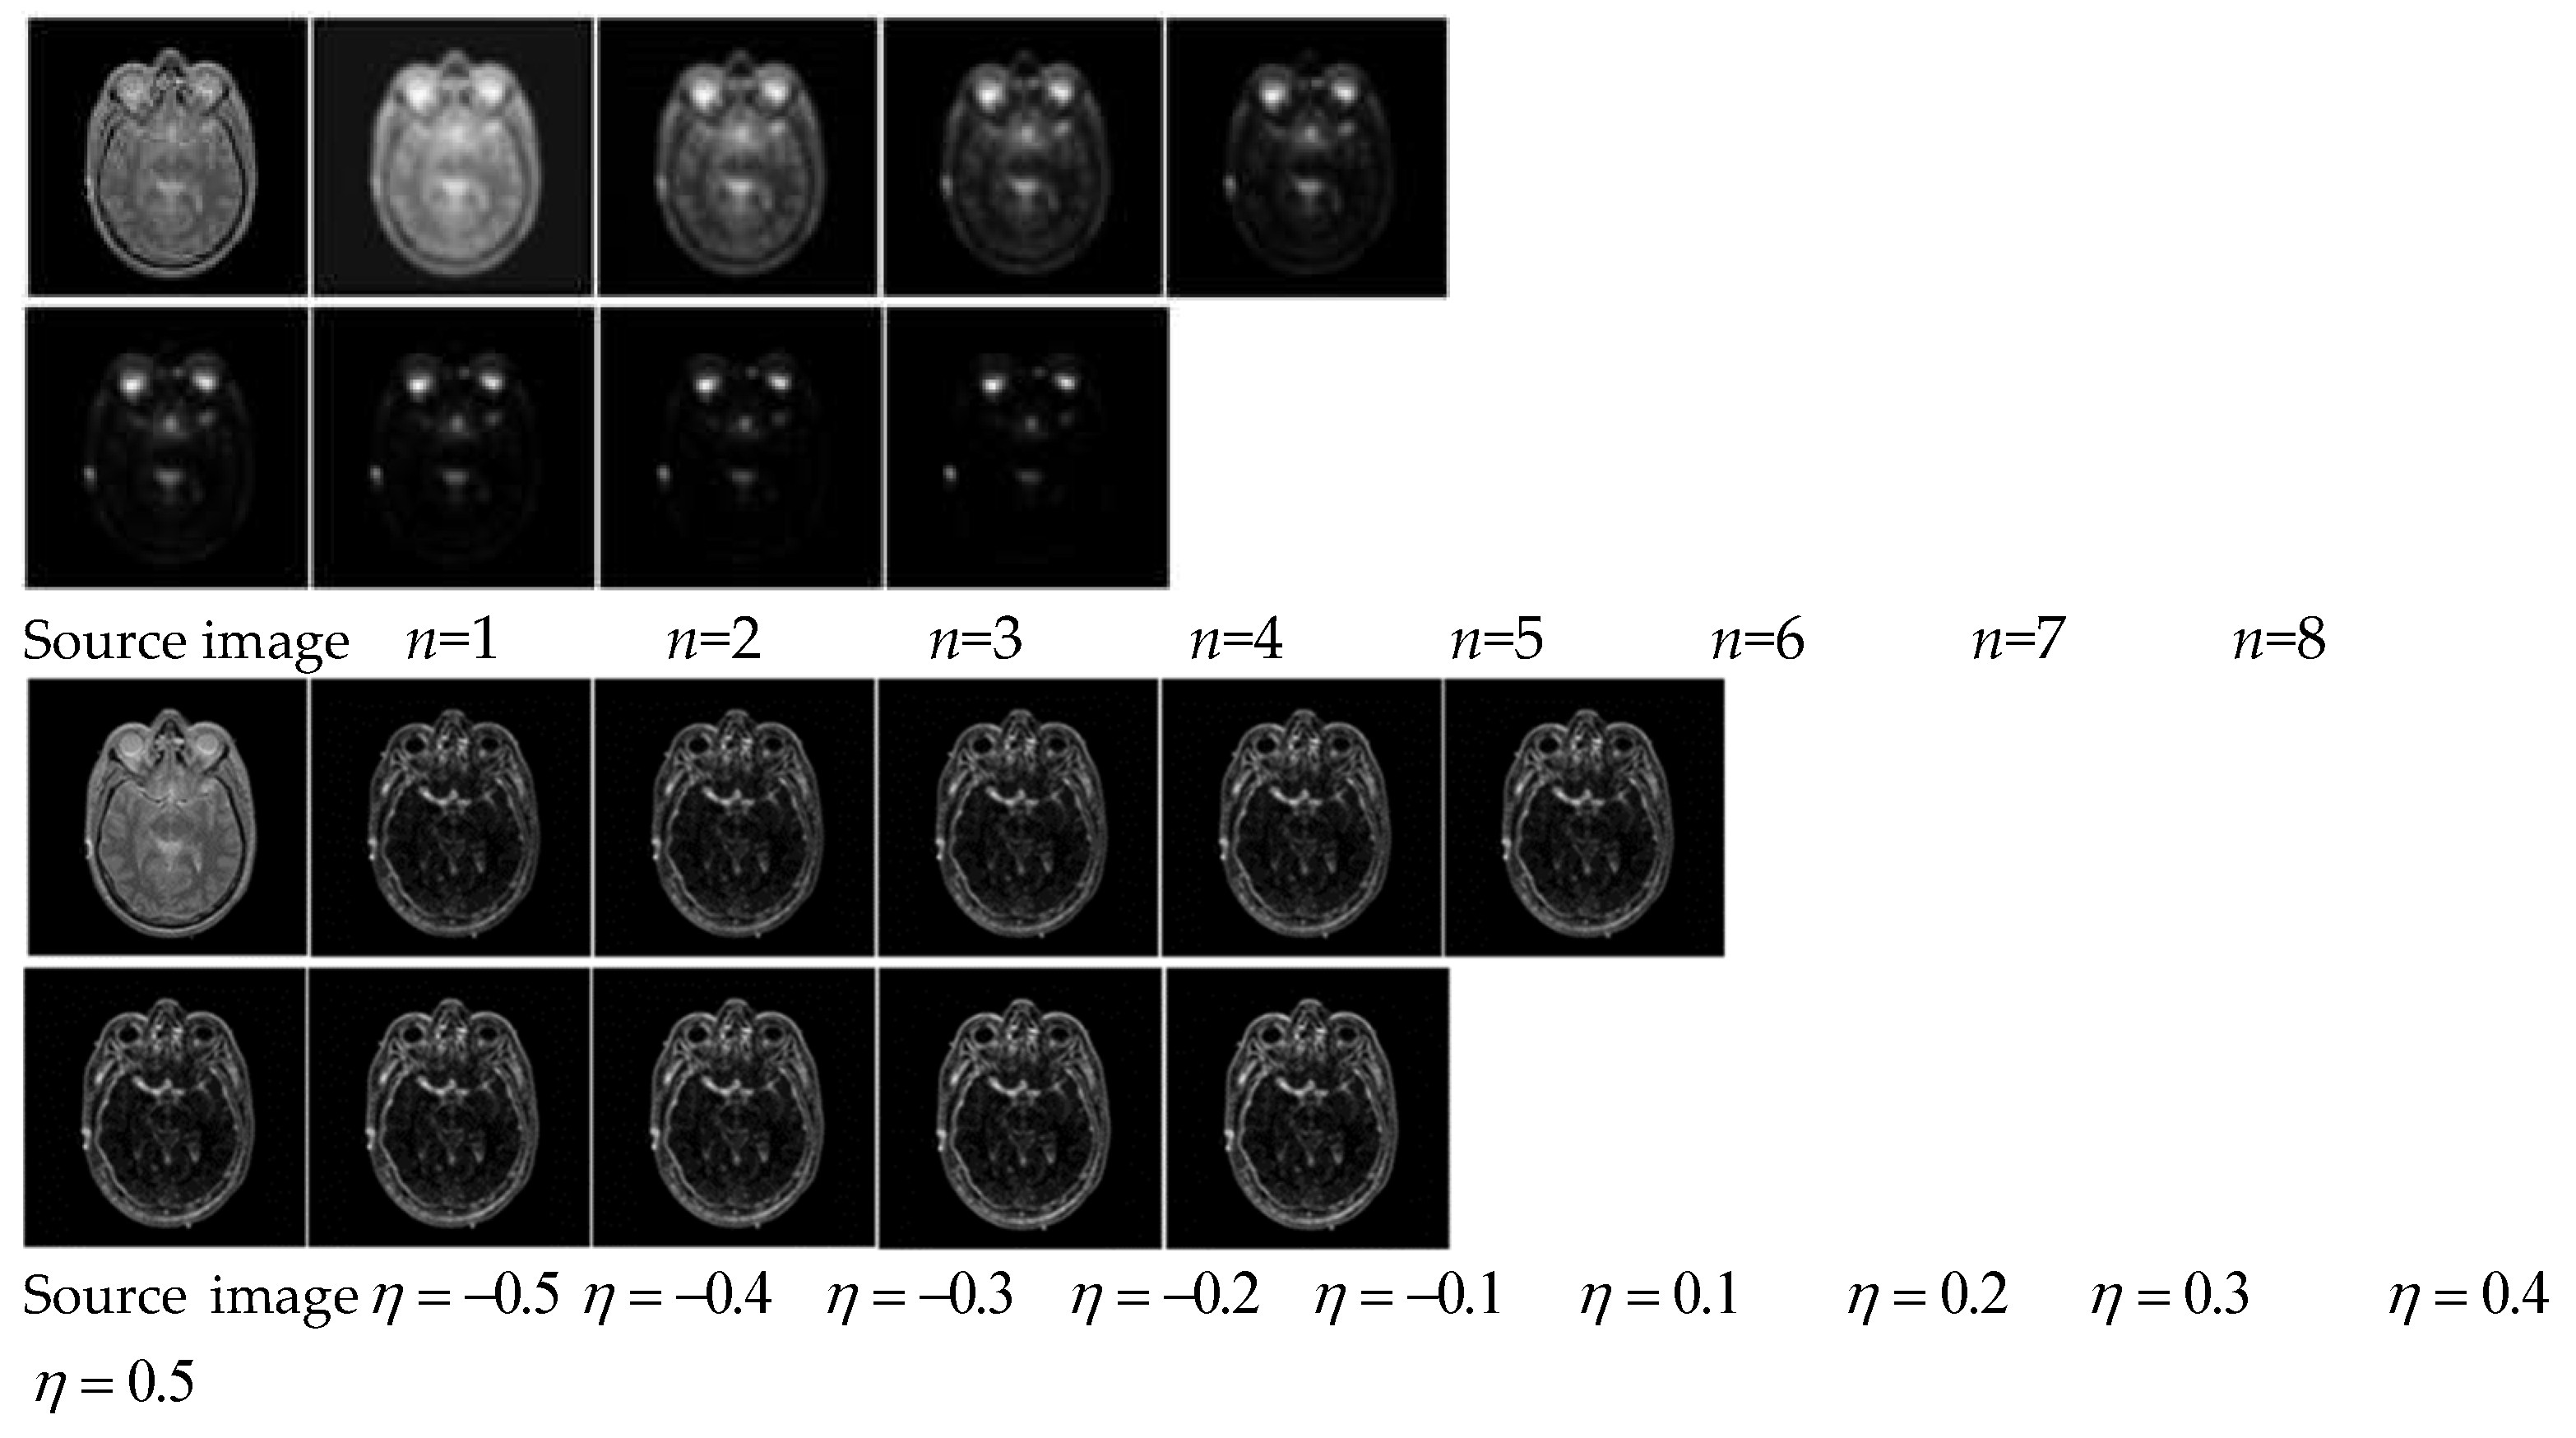

In addition to the above general settings, variable n and variable η are the key parameters to affect the luminance contrast and the orientation contrast separately, and the parameters setting through quantitative experiments are shown in Figure 3. It can be seen that variable n will affect luminance contrast and the retention of effective information in subsequent fusion results. On the basis, we set n=3 as a compromise. As increase of variable η , texture structure of the source image is clearer, and it is conducive for extracting orientation contrast information. On the basis, we set η = 0.5 .

Figure 3. Parameters setting through quantitative experiments: The first line indicates the effect of n on luminance contrast, and the second line indicates the effect of η on orientation contrast.